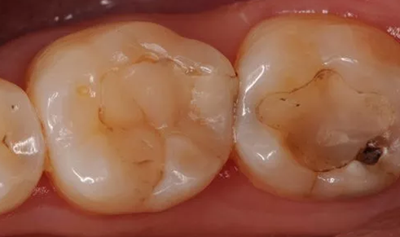

八、繼發(fā)齲

(一)原因

腐質(zhì)未去凈。充填體邊緣不密合:原因包括修復(fù)體飛邊折斷;樹脂材料自身聚合收縮;夾在充填體和洞側(cè)壁或齦壁的充填材料溶解。

如 PPT22 圖示下為臨床治療常見的邊緣白線,造成了充填體邊緣的不密合,圖上是治療的時腐質(zhì)沒有去除干凈,繼續(xù)發(fā)展以后出現(xiàn)摸尋狀的改變。